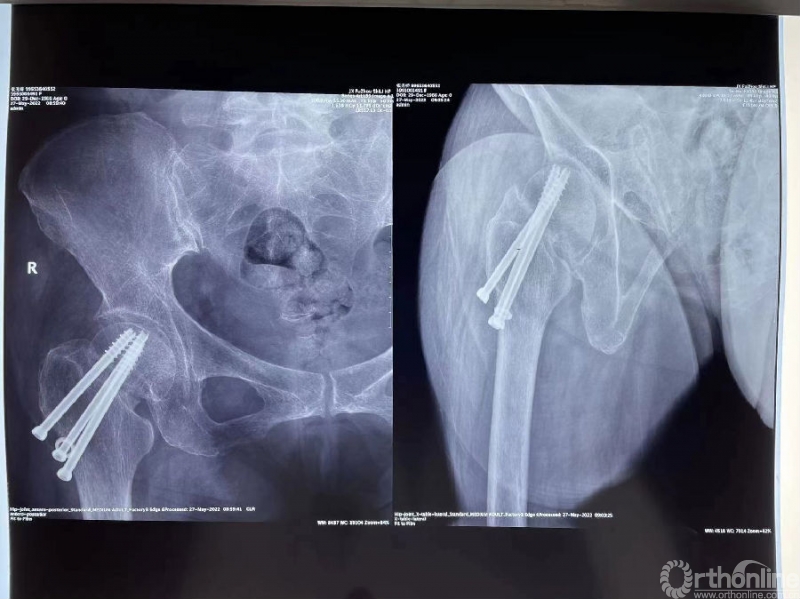

手术过程:

(1)髂骨自体取骨,取适量松质骨;

(2)取出锁定钢板上的第4颗螺钉;

(3)DAA入路,切开关节囊;

(4)彻底刮除骨折断端纤维瘢痕组织;

(5)植入自体松质骨+BMP-2改善局部生物学环境;

(6)植入1/3管形板支撑,改善骨折愈合的生物力学环境。

影像学资料